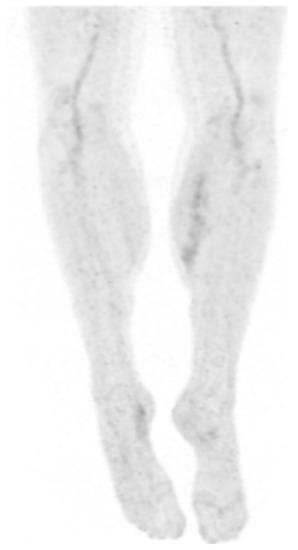

2. Case Presentation